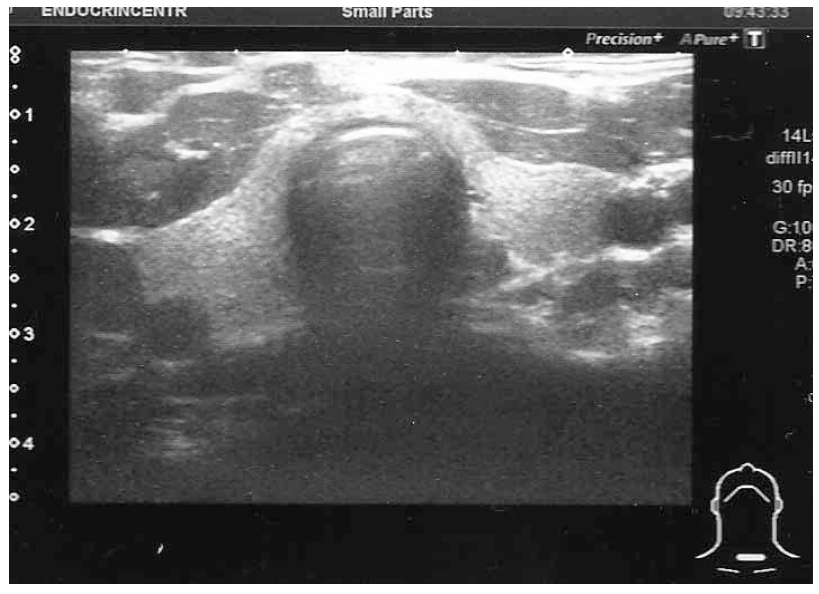

15. Fig. 7. Absence of echographic signs of autoimmune thyroid disease | |